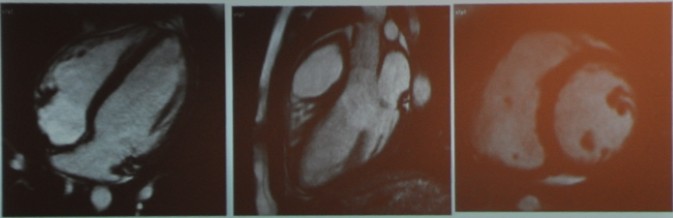

图1 正常心脏磁共振电影成像

(从左到右依次为四腔心切面、三腔心切面、短轴切面[原为动图])

磁共振电影成像非常清晰,辨别度高,这是磁共振现在成为心脏容量和射血分数评估的“金标准”的原因。